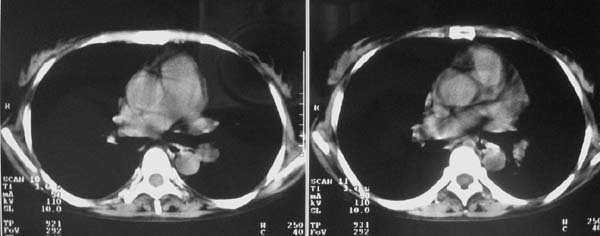

以下是引用zjzjr在2007-9-20 12:29:00的发言:[br]双肺磨玻璃改变,考虑肺水肿.

以下是引用yangzongshan在2007-9-20 18:29:00的发言:[br]两肺毛玻璃样改变,其内可见肺纹理影,无胸腔积液,故考虑肺泡蛋白沉积症

以下是引用276894491在2007-9-20 13:40:00的发言:[br]考虑肺水肿;外源性过敏性肺炎不排除。

以下是引用逸风在2007-9-20 20:45:00的发言:[br]两肺磨玻璃样改变,临床病史短,发热,考虑病毒感染合并右肺代偿性肺气肿.待排肺水肿,病史短,不支持肺泡蛋白沉着症.